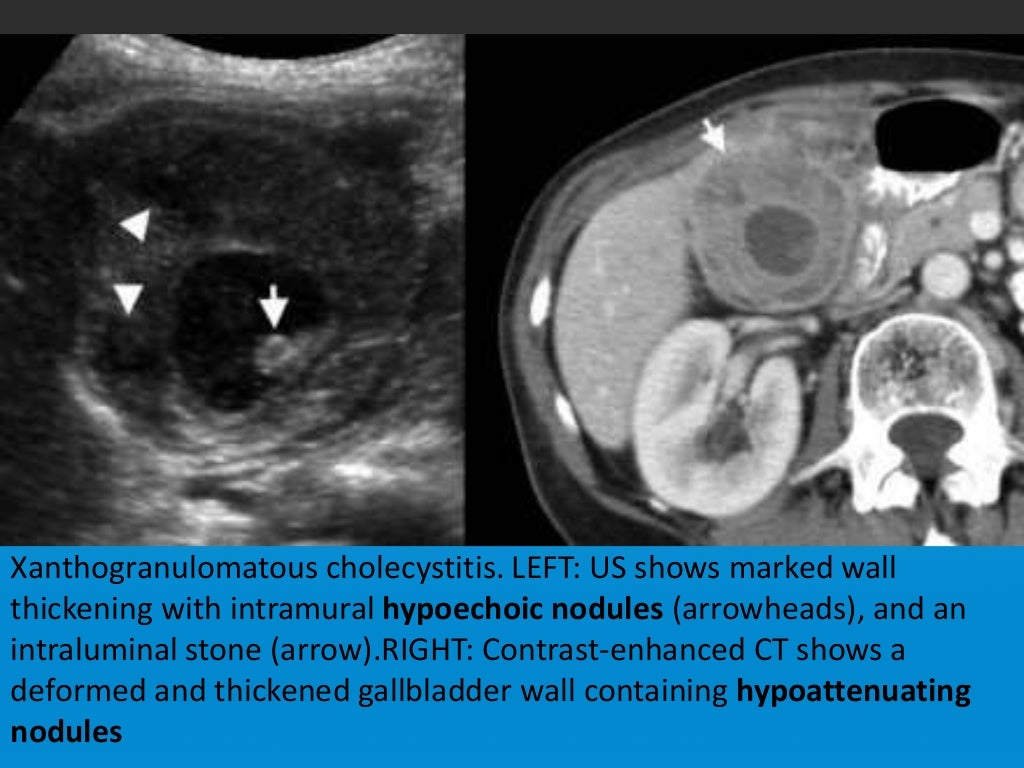

Diffuse Gallbladder Wall Thickening Differential Diagnosis AJR